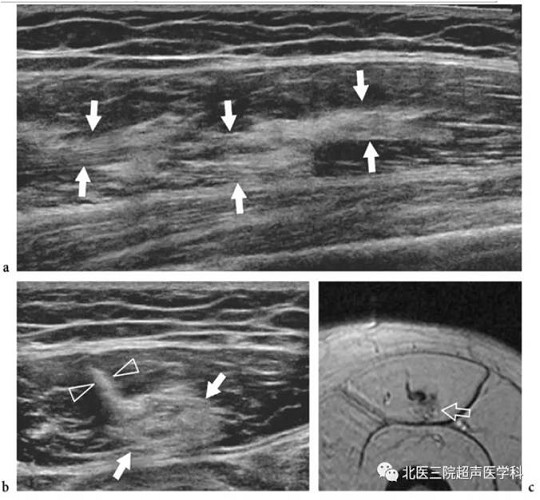

超声损伤1级的2个病例。a、b病例1:股直肌中1/3部分的超声图像,a短轴切面b长轴切面显示一个围绕中心腱的边界不清的高回声区(白箭头),与水肿和出血性改变相关。注意肌肉(箭头)外部的正常表现;c-e病例2:短轴扫查股直肌c近端至e远端的超声切面图像,显示中心腱(直箭头)和邻近的肌纤维(弯箭头)的进行性肿胀和回声减低(白箭头)表现伴随小血肿(星号),说明肌腱拉伤